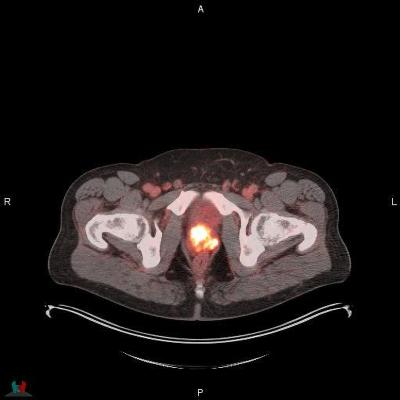

POSLUMA (flotufolastat F 18) PET/CT image showing uptake in the prostate gland, consistent with primary prostate cancer. Photo courtesy of Blue Earth Diagnostics

POSLUMA is approved in the United States for positron emission tomography (PET) of prostate-specific membrane antigen (PSMA) positive lesions in men with prostate cancer with suspected metastasis who are candidates for initial definitive therapy or with suspected recurrence based on elevated serum prostate-specific antigen (PSA) level.